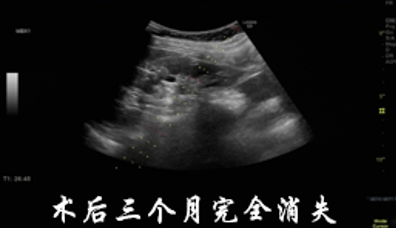

从急诊转诊到介入科就诊,再到住院检查、治疗、出院,整个流程无缝衔接。张奶奶上午办理住院后完成相关术前检查,下午就顺利接受了硬化治疗,术后颈部胀痛明显缓解,第二天各项指标平稳后便康复出院,全程仅用两天时间。

这种 “检查 - 诊断 - 治疗 - 康复” 一站式诊疗模式,正是介入与血管外科的核心优势。无需患者在多个科室间来回奔波,专业团队全程跟进,既缩短了诊疗周期,又减少了患者的痛苦和家属的照料负担。